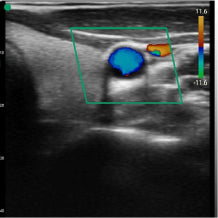

Real life images

Our devices reproduce excellent image quality.